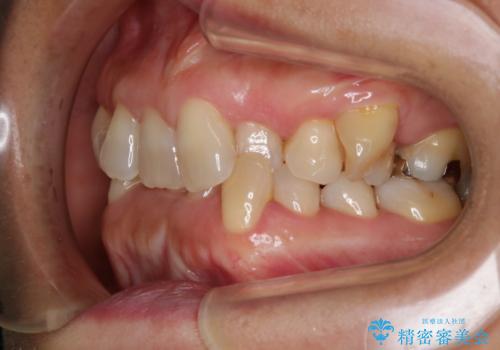

- 上下の歯のがたつきと、噛み合わせが深いことを気にされてご相談にいらした方です。噛み合わせに参加していない歯を抜歯してインビザラインにて治療を行いました。

一般的に噛み合わせの深い方へのインビザライン治療は適応が難しいとされていますが、今回は噛む力を上手にコントロールできたことと、内側に入り込んでいた前歯の角度を調整したことで下の歯がしっかり見えるようになりました。短期間で劇的に見た目が改善し、大変喜んでいただけました。